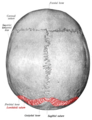

Parietal bones (above) and occipital bone (below).

Lambdoid suture seen from above.

Lambdoid suture seen from inside.